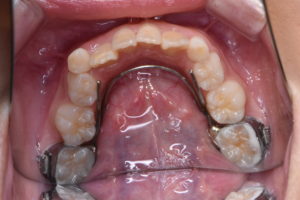

Ⅰ期治療として上顎には急速拡大装置、下顎にはバイヘリックスを用いることで狭窄歯列の拡大を行い、前歯部のスペース不足の改善を行った後に、マルチブラケットを併用することで歯列の配列を行った。前歯部の配列終了後舌側に保定ワイヤーで歯牙の固定を図り治療終了となった。

Ⅰ期治療の場合、治療終了時点では側方歯群に乳歯が残存しているため、永久歯の交換を待ち正常歯列となるか経過観察を行う。